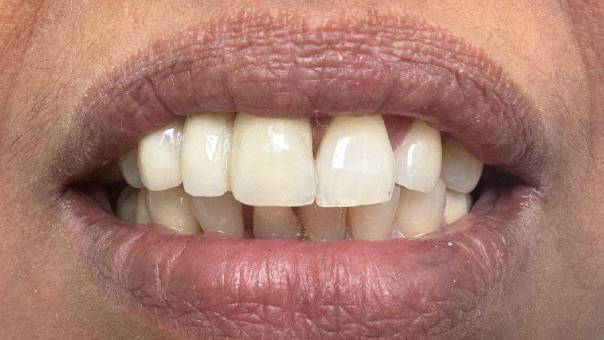

Patient Concern: A middle-aged female patient visited our clinic with a primary concern about spacing in her upper front teeth. She was particularly self-conscious about the gap and was seeking an aesthetic and long-lasting solution.

To enhance both function and aesthetics, we utilized a creative restorative approach. The patient's peg lateral was reshaped to function as a canine, and the missing tooth was replaced as a Lateral Incisor—restoring symmetry and balance to her smile.

The Final Touch: The patient opted for a Zirconium bridge, known for its strength, durability, and natural appearance. The result was a seamless, natural-looking smile transformation.

Outcome: The patient was extremely satisfied with the outcome. Her smile was not only corrected functionally but also dramatically enhanced in appearance—boosting her confidence and overall satisfaction.